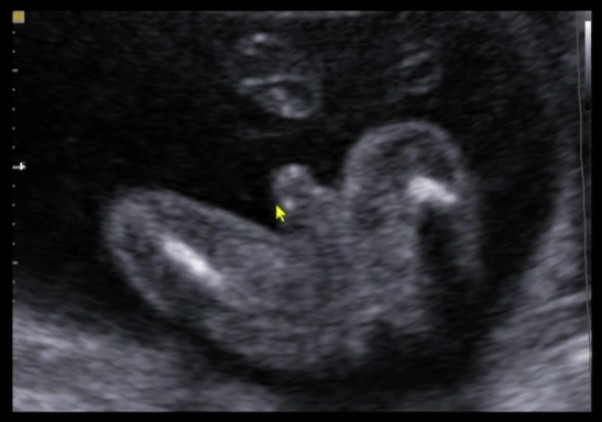

jakie to było piękne kiedy na szybkim podglądzie lekarz powiedział "chłopak jak malowany" :D :D :D radość taty nieograniczona moja też :) więc kolorem przewodnim będzie błękit ale sowy zostają :D nasz synek się ujawnił :D